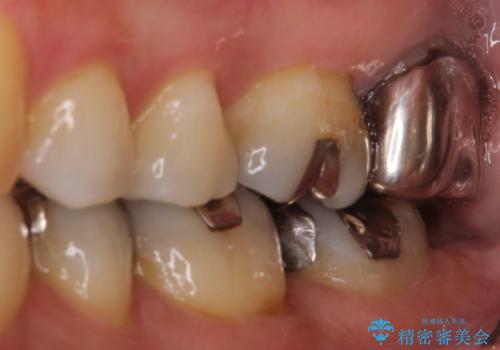

【根管治療】未処置根管を有した歯の再根管治療

- 定期検診にて虫歯を見つけたため、根管治療からオールセラミッククラウンによる修復治療を行いました。

上顎第一大臼歯の近心根にはほとんどの場合、神経の管が二本あることが多いです。顕微鏡を用いることで見逃すことなく治療が行えました。